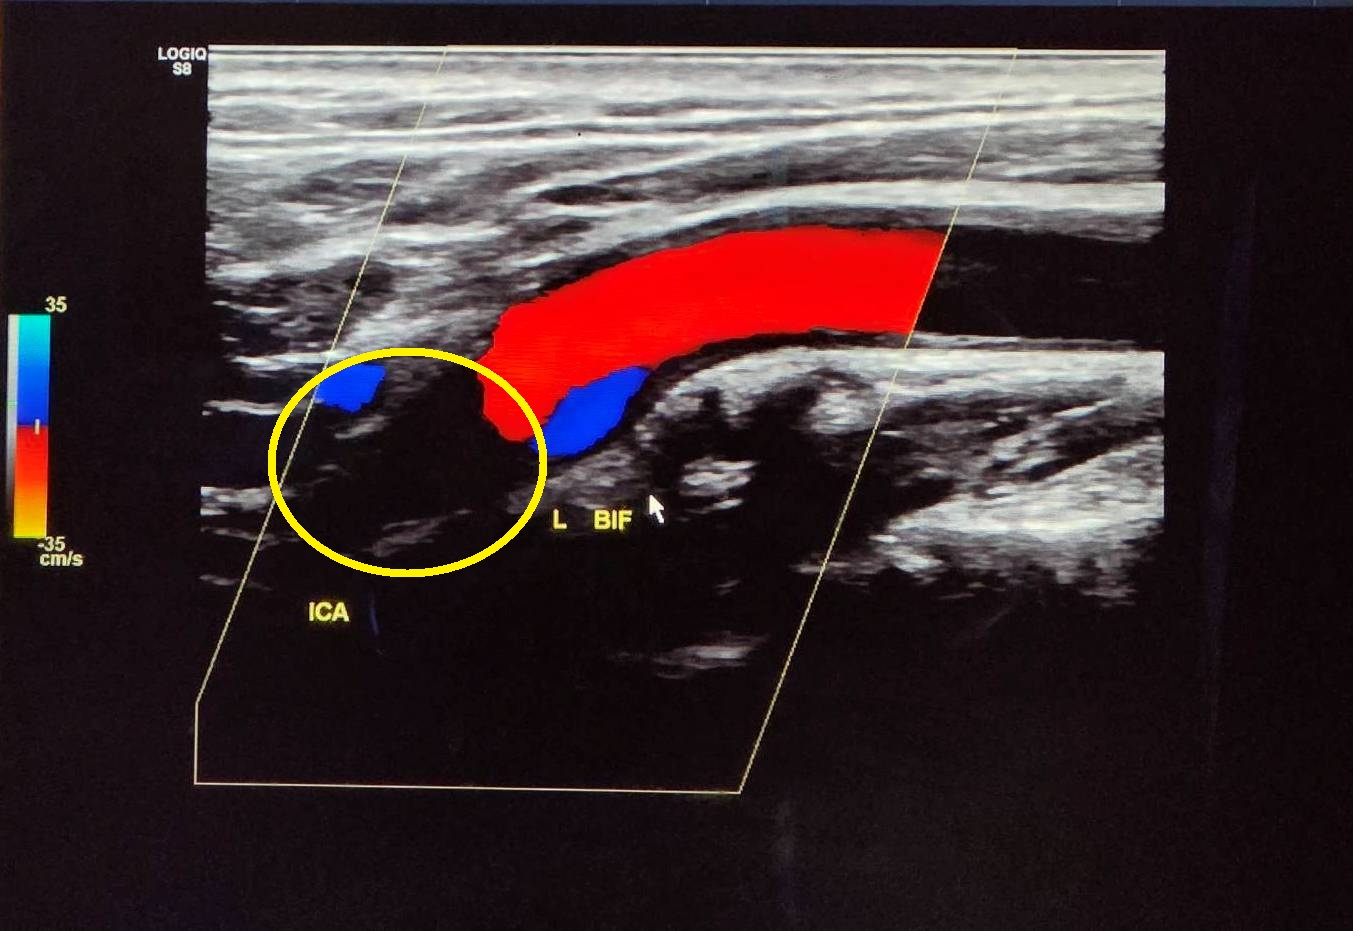

透過頸動脈超音波發現,病人左側內頸動脈已完全阻塞(黃圈處)。照片:大千綜合醫院提供